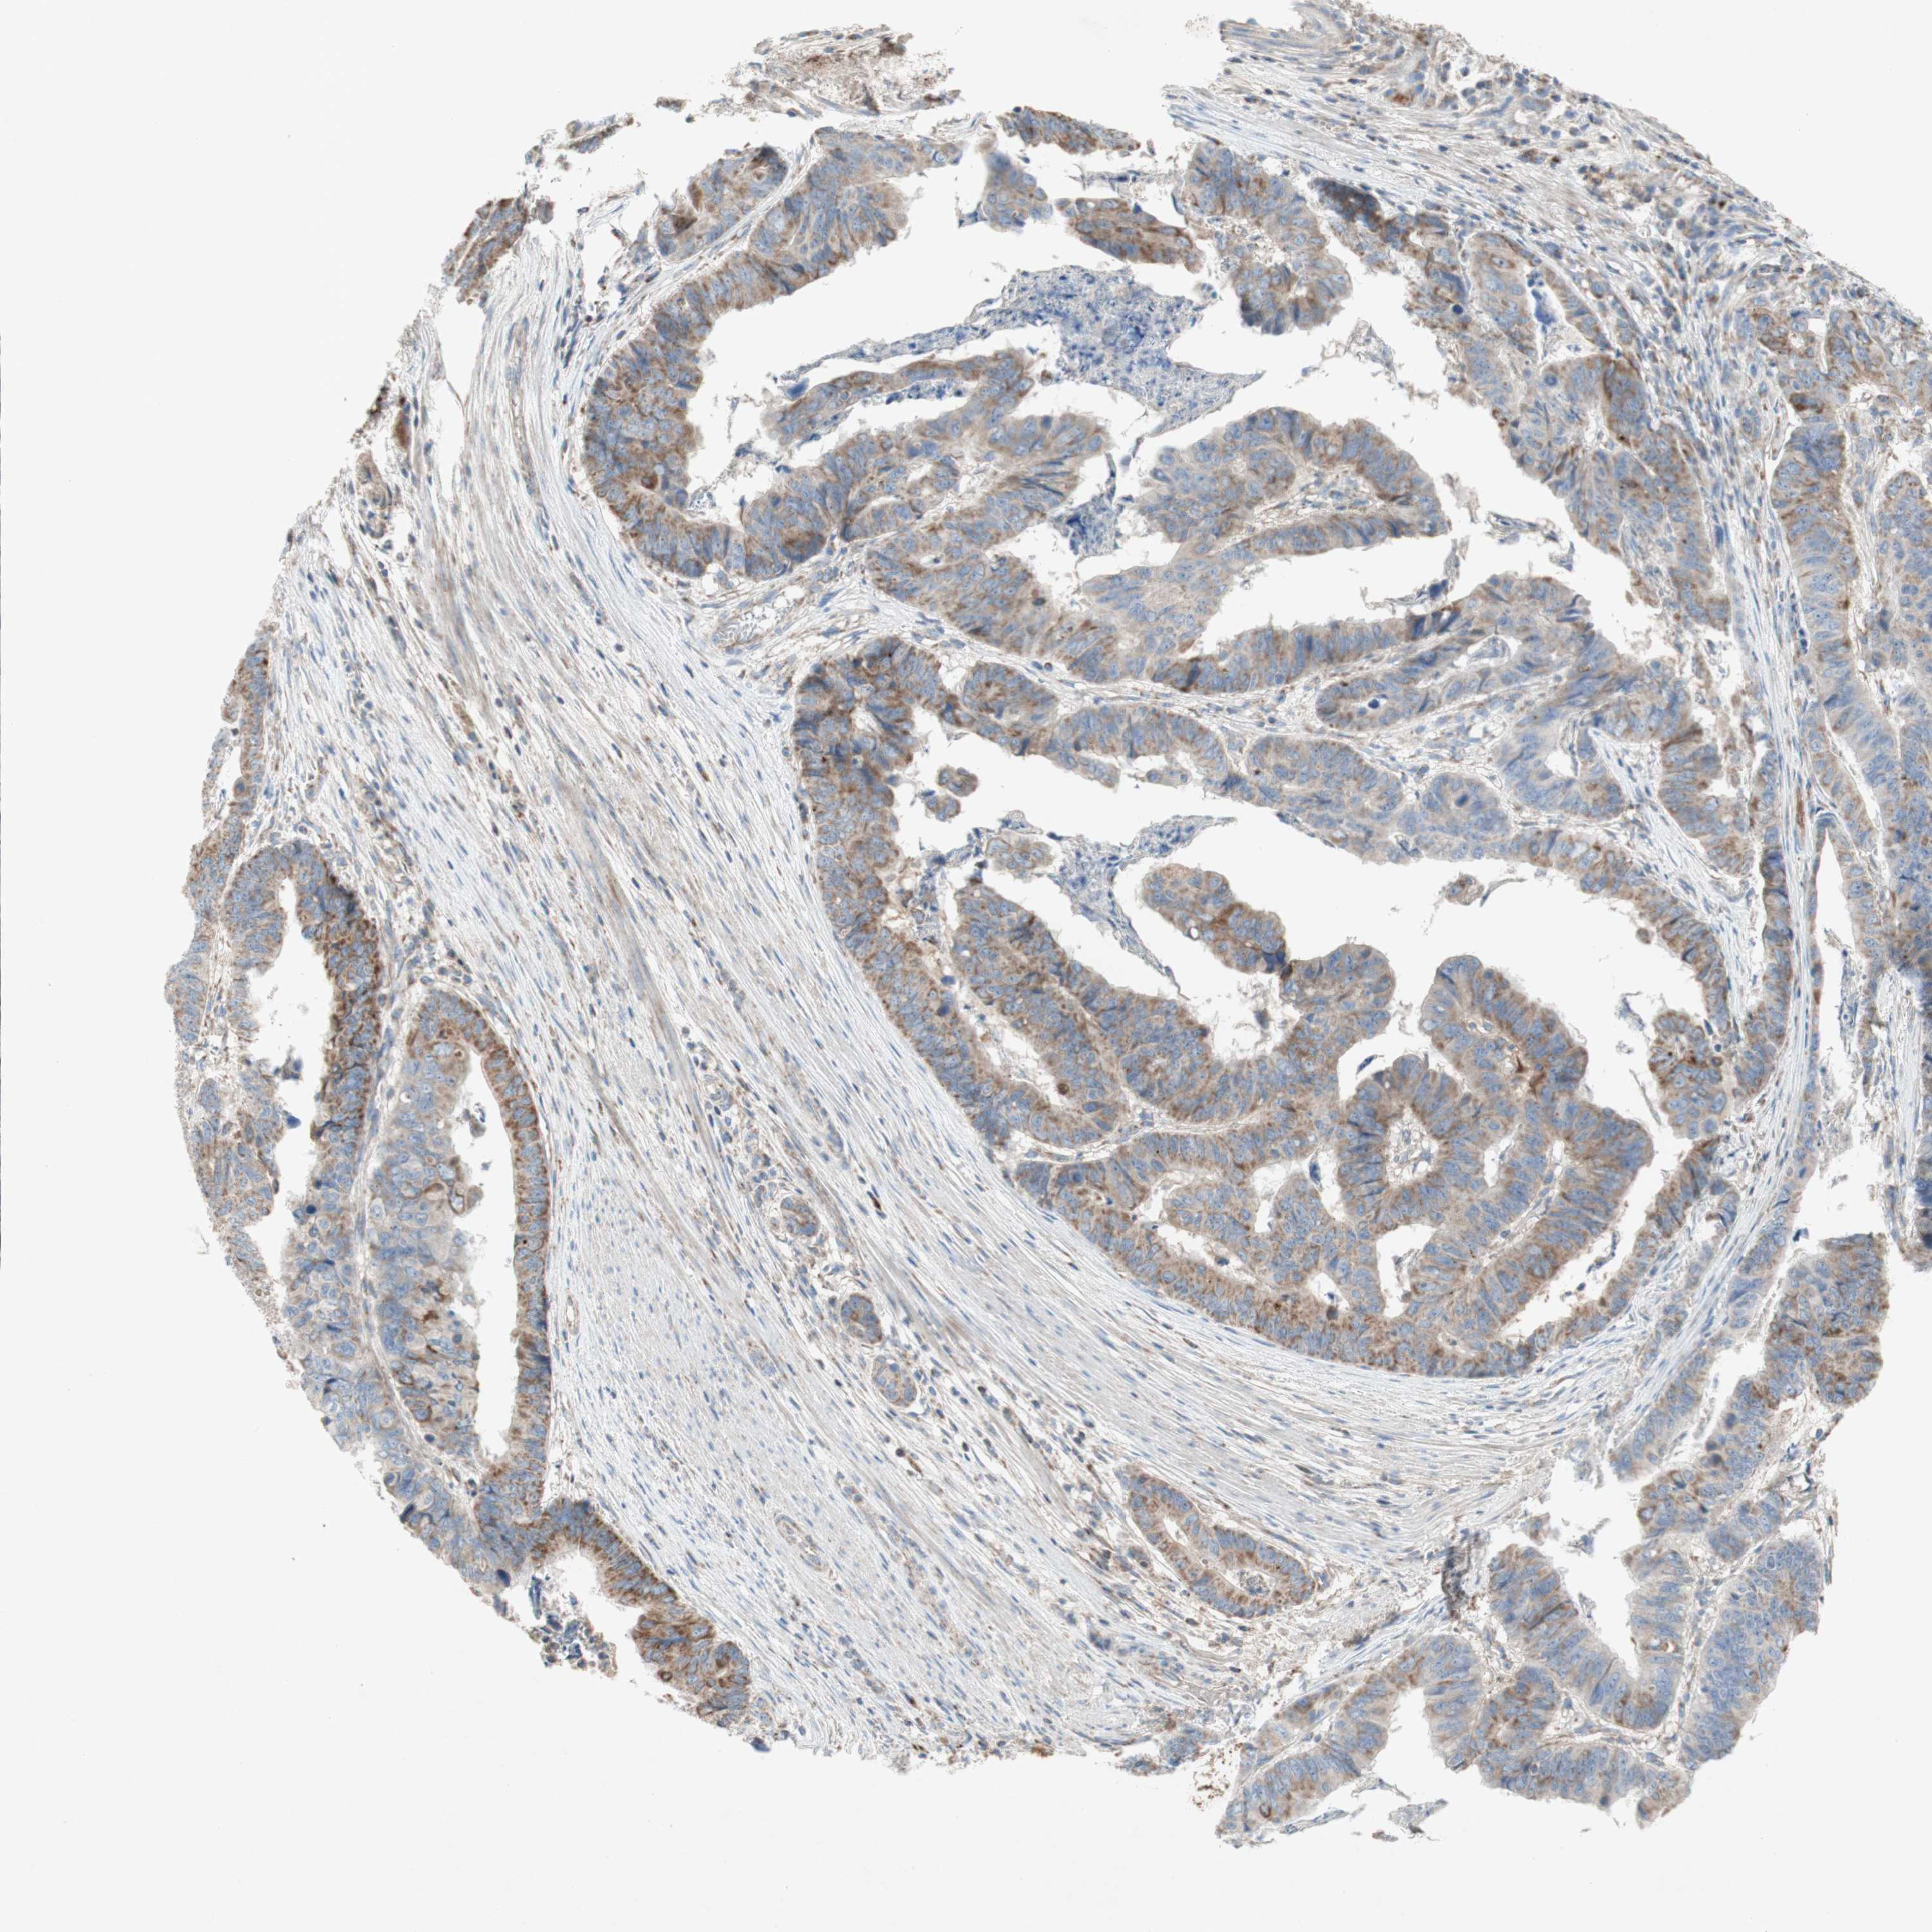

STOMACH CANCER - Protein expressioni

A mouse-over function shows sample information and annotation data. Click on an image to view it in a full screen mode. Samples can be filtered based on level of antibody staining by selecting one or several of the following categories: high, medium, low and not detected. The assay and annotation is described here.

Note that samples used for immunohistochemistry by the Human Protein Atlas do not correspond to samples in the TCGA dataset.

Antibody stainingi

Antibody staining in the annotated cell types in the current human tissue is reported as not detected, low, medium, or high, based on conventional immunohistochemistry profiling in selected tissues. This score is based on the combination of the staining intensity and fraction of stained cells.

Each image is clickable and will lead to virtual microscopy that enables deeper exploration of all samples and also displays staining intensity scores, fraction scores and subcellular localization as well as patient and tissue information for each sample.

HPA002868

CAB009822

CAB068233

CAB068234

CAB068235

Adenocarcinoma, NOS

Adenocarcinoma, High grade